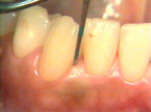

| Esta serie de

imágenes muestra el diagnóstico y tratamiento de la periodontitis

moderada en una mujer de 35 años de edad. Se observa

inflamación por el cambio de color, aspecto de la superficie y por la consistencia del margen gingival. Si el margen

gingival está flojo cuando aplicamos aire de la jeringa triple es una indicación de inflamación

del tejido. |

Se sondea las

bolsas periodontales en bucal, mesial, distal y palatino. Observandose

la profundidad y registramos el sangrado si lo hubiere. La destrucción del

periodonto es generalmente irregular y es necesario mover la punta de la sonda en varias direcciones para encontrar el sitio más profundo

en cada superficie. |

Note la

inflamación gingival y la presencia de placa supragingival en los

dientes. En bucal del segundo molar hay una bolsa profunda al

sondaje y placa supra y subgingival al movimiento lateral de la sonda. |